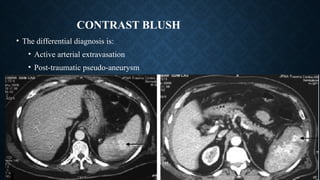

CONTRAST BLUSH

• The differential diagnosis is:

• Active arterial extravasation

• Post-traumatic pseudo-aneurysm

• Post-traumatic AV fistula

CONTRAST BLUSH • Thedifferential diagnosis is: • Active arterial extravasation • Post-traumatic pseudo-aneurysm • Post-traumatic AV fistula